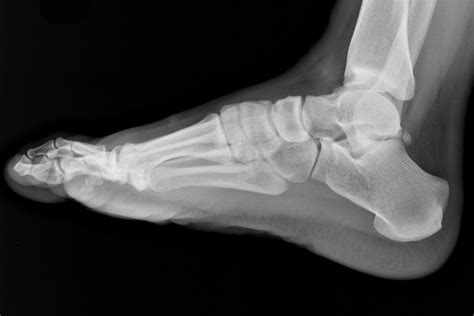

The patient is positioned on the X-ray table, and the foot is placed in a specific position to capture the desired views. Common views include:

• Lateral view: Shows the side of the foot.

Interpreting a Normal Foot X Ray involves a thorough examination of the images to ensure that all structures appear normal. Key areas of focus include:

Bones

The bones of the foot, including the tarsals, metatarsals, and phalanges, should be clearly visible and aligned properly. Any fractures, dislocations, or deformities would be immediately apparent.

Bone Spurs

Bone spurs are bony projections that develop along bone edges. They can cause pain and discomfort and are often associated with conditions like osteoarthritis. X-rays can identify the presence and location of bone spurs.